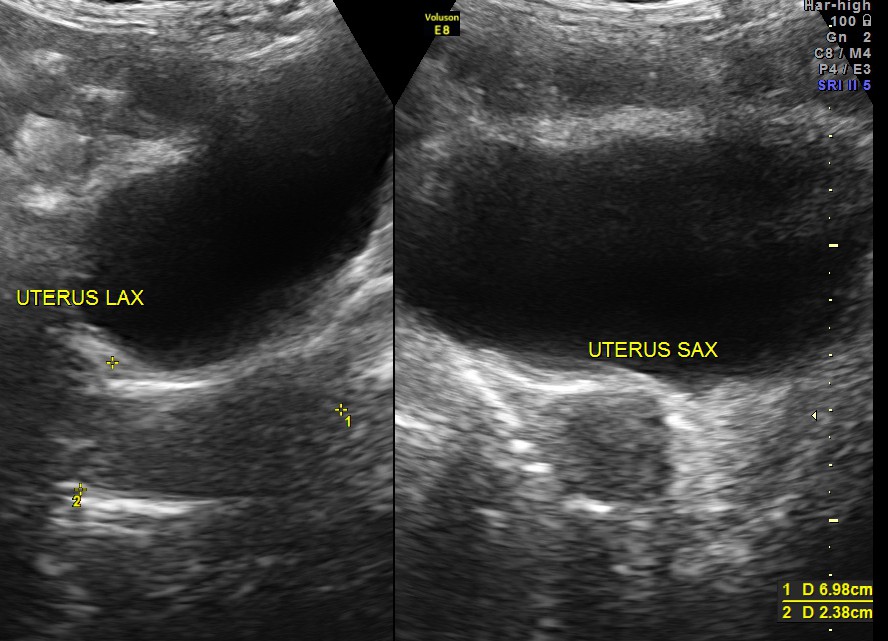

Pelvis appeared to be normal.